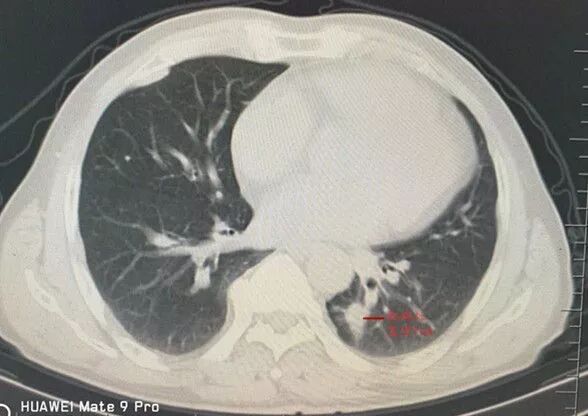

病例二:患者張某某,男,62歲,主因咳嗽、咳痰入住我院呼吸二科,入院后胸部CT顯示左肺下葉后基底段近脊柱旁一小結節(jié)影,先行氣管鏡檢查未發(fā)現異常,為明確該結節(jié)性質于2017年12日19日與呼吸二科張占強主任通力合作對該患者實施了CT引導下經皮肺微小結節(jié)穿刺活檢術,術程順利。

肺窗示左肺下葉背段脊柱旁一最大徑約12mm軟組織結節(jié)